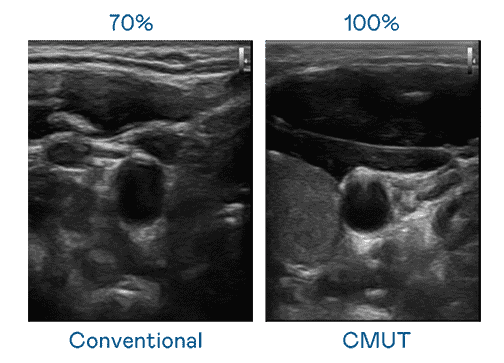

CMUT 技术是一种用电容式微机电元件来产生超音波讯号的技术。。。与传统 PZT 压电式技术相比,,,,CMUT 频宽增加 30%,,,更宽频的超音波讯号让影像解析度大幅提升,,,,是实现高影像品质医疗超音波扫描、、、、促进精准医疗发展的关键技术。。

大频宽带来超清晰影像

超音波影像的解析度高低,,,首先取决于探头能发出的讯号频宽。。。。www.z6.com CMUT 可提供高清晰的超音波讯号,,提供高频宽、、、、高灵敏度、、、影像纹理细节更高的超音波影像,,,协助医护人员缩短影像判读时间及利用精准的医疗影像进行诊断。。。